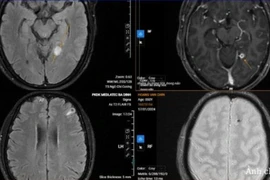

Sán chi chít làm tổ trong não vì... thói quen ăn đồ tái sống

Đau đầu nhiều ngày, người đàn ông đi khám bất ngờ phát hiện sán chi chít làm tổ trong não.